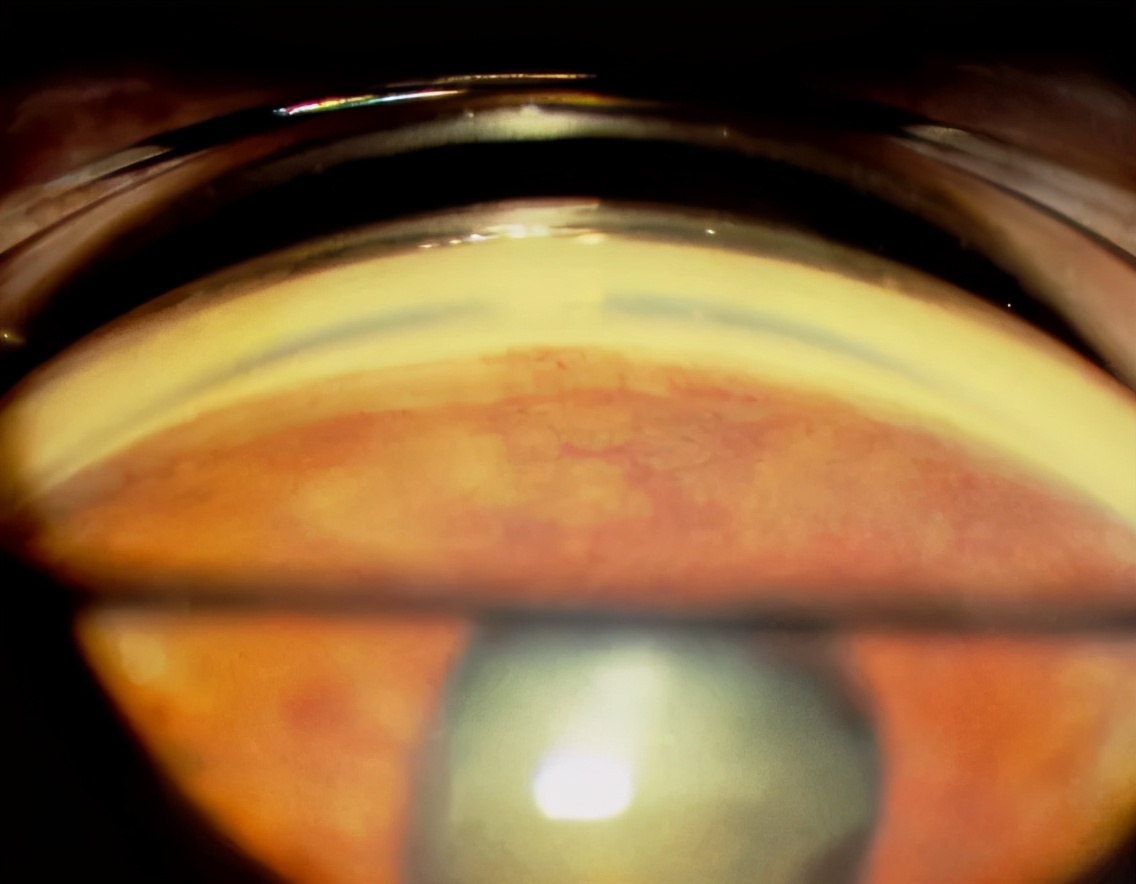

图2. 新生血管性青光眼:虹膜瞳孔边缘的新生血管,前房角新生血管,继发性房角闭合,虹膜和小梁网紧密粘连

图3. 虹膜瞳孔边缘的新生血管

图4. 前房角的新生血管导致房角再次关闭